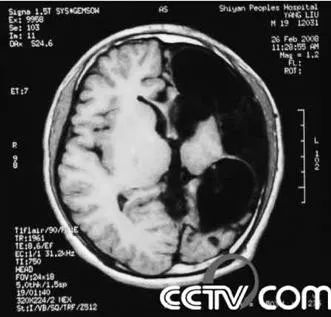

2009年2月,中國中央電視台CCTV-10科教頻道《科學探索》節目講述了一個“半腦人”的故事。這個病人在剛出生不久就發高燒而被診斷為腦膜炎,當時醫生認為他會有後遺症。但是他的病症不久就消失了,沒有發現異常而一直健康成長。到了12歲的時候,他出現了癲癇症狀。隨後,癲癇發作間隔逐年縮短。在他17歲時,癲癇發作間隔已經按星期來算了,家人只好帶他到武漢的大醫院診治。下圖是他的腦部CT片,從中能夠看到他的一側大腦嚴重病變萎縮。

一側嚴重萎縮了的大腦

醫生看到這種情況,決定摘除已經喪失了基本功能並且嚴重萎縮的一側大腦。手術後,病人的癲癇症狀徹底消失,而且各種表現也一如常人。醫生推斷,在他小時候那次得病之後,一側大腦就逐漸失去作用,另一側逐步完整地接管了大腦的所有功能。這個例子似乎支持了人的大腦在正常情況下利用率不高這一結論,雖然對此結論尚有爭議。